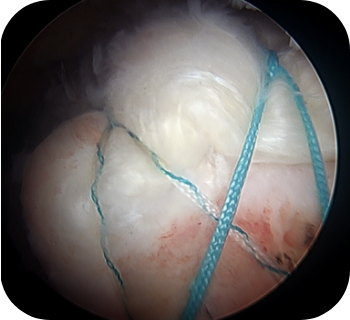

이식된 피부조직이 부분적으로 봉합된 회전근개를 보강해주어 힘을 더 받을 수 있으며, 봉합된 힘줄의 치유능력 또한 향상시킵니다.

파열 범위가 큰 광범위 파열인 경우, 가능하면 일차 봉합술을 시행하는 것이 바람직하나, 내측으로 말려들어간 힘줄을 무리하게 당겨 봉합을 할 경우 재파열이 빈번하게 일어날 수 있습니다. 우선 관절경으로 견봉 성형 및 점액낭을 제거한 후 파열의 정도와 모양을 확인하고, 복원 불가능한 파열에서는 부분 복원술을 시행한 이후 피부조직이식술을 시행하게 되는데, 이는 노출된 상완 골두를 덮어주고 봉합한 힘줄을 보강시켜줄 수 있는 방법입니다.

▲ 회전근개 봉합술 후